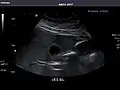

Gallbladder -

Gallbladder

Gallbladder: No stones, wall thickening, or pericholecystic fluid.

Common Bile Duct: Nondilated measuring 1.3 mm at the level of the porta hepatis.